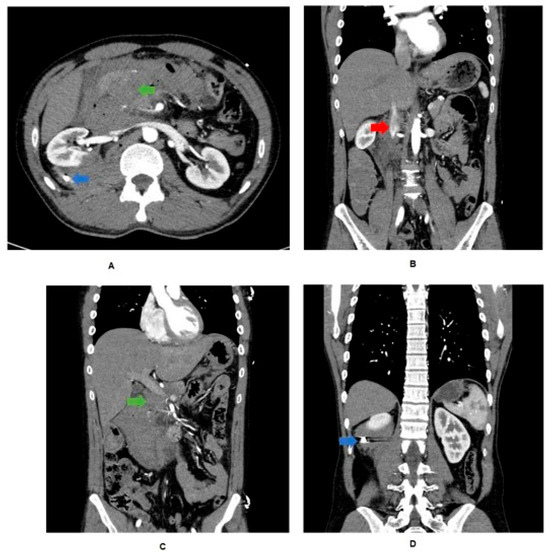

During the procedure, a non-expanding retroperitoneal hematoma was identified, indicating a venous source of hemorrhage with retroperitoneal self-tamponade. Access to the hematoma revealed anterior and posterior defects in the infrarenal IVC (AAST grade III abdominal vascular injury). Hemostasis of the IVC was achieved by proximal balloon catheter occlusion, with venorrhaphy of the posterior and anterior IVC defects using 6-0 prolene (Figure 2). The total IVC occlusion time was approximately 6 min. A right nephrectomy was performed to control hemorrhage, along with an extended right hemicolectomy. The bullet was retrieved during the procedure and sent with the operative specimens for histopathology and subsequent forensic pathology. Intra-operatively, the decision was made to perform a pancreaticoduodenectomy due to a 4 cm defect in the head of the pancreas and associated duodenal perforation (Figure 3 and Figure 4), representing an AAST grade V pancreatic injury. During the procedure, the patient had an estimated blood loss of 800 mL, requiring a further unit of packed red cells and one unit of cryoprecipitate. Cell salvage was not used.

Figure 3. Intra-operative photograph of head of pancreas (P) and duodenum (D), with arrow indicating a 4 cm defect in head of pancreas.